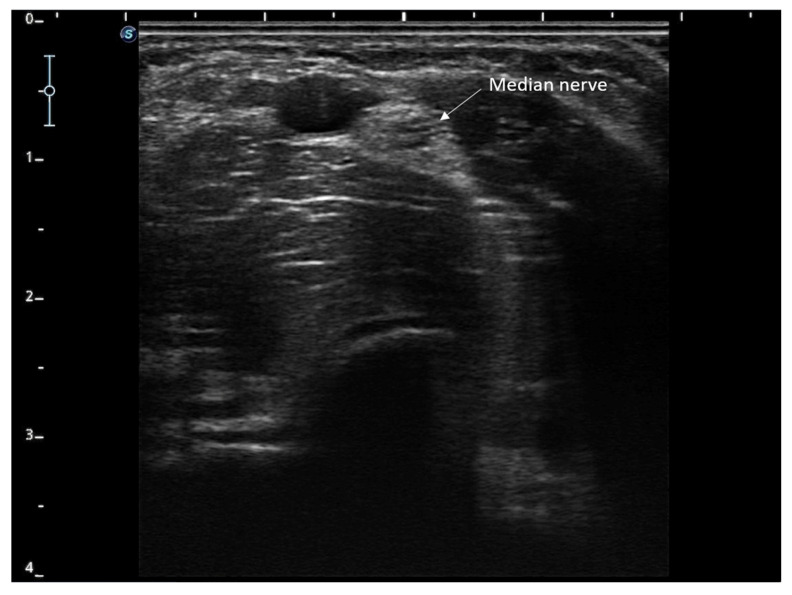

Background and Clinical Significance: Chemotherapy-induced peripheral neuropathy (CIPN) is a frequent and limiting complication of oncological treatment, particularly in patients receiving oxaliplatin. Its onset can significantly affect the quality of life and compromise the continuity of the antineoplastic therapy. Due to the limited efficacy of available pharmacological therapies, percutaneous electrical nerve stimulation (PENS) has been proposed as a non-invasive alternative for symptom management. Case presentation: We report the case of a 75-year-old woman with colorectal adenocarcinoma who developed CIPN following oxaliplatin administration. She underwent a 12-week course of PENS targeting the median nerve, with weekly sessions conducted without interruption of chemotherapy and without adverse effects. The patient showed progressive improvement in neurosensory symptoms, as measured by the EORTC QLQ-CIPN20 questionnaire. Quantitative sensory testing revealed normalization of thermal and vibratory sensitivity and improved mechanical detection thresholds. The cumulative oxaliplatin dose was maintained throughout treatment. Conclusions: PENS may offer an effective and safe therapeutic option for managing CIPN, enabling symptom control without compromising oncological treatment. This case supports the need for controlled clinical trials to confirm efficacy and establish standardized protocols.